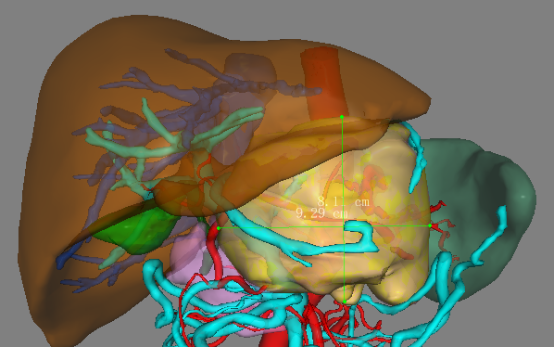

图1:上腹部CT显示胰腺巨大肿瘤

“CT表现符合胰腺神经内分泌肿瘤,穿刺也证实无误,但是瘤体实在太大,直径约12cm左右,腹腔内的门静脉、肠系膜上静脉、脾静脉以及腹腔干这些重要血管统统包绕进去了,且与周围结肠系膜也有累及。”

曹利平教授带着团队成员逐一分析,隐藏在瘤体附近的血管就像埋在炸弹旁的导火索,稍有不慎,便会引爆这颗瘤体炸弹,要想把肿瘤完整切除,更是难上加难。